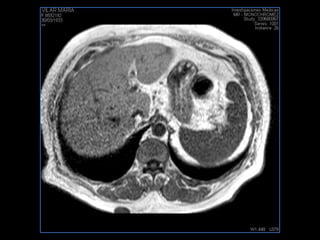

PROTOCOLO abdomen COR T2, AXIAL supresion grasa AX T1 +SAG T2  CON   GADOLINIO :  COR T1+AX T1(DIN) SAT: NO  FASE: RL THK: 6MM  COIL:  GAP: (FACTOR 1.4) 2MM FOV: 40 CM NEX:2 SINCRONIZACION RESPIRATORIA EN 3 O 4 CICLOS ALE

PROTOCOLO hígado graso AXIAL in phase y out phase AX T1 y AX fat sat +SAG T2  CON   GADOLINIO :  COR T1+AX T1(DIN) SAT: NO  FASE: RL THK: 4MM  COIL:  GAP: (FACTOR 1.4)  FOV: 40 CM NEX:2 SINCRONIZACION RESPIRATORIA EN 3 O 4 CICLOS ALE

resonancia de abdomen